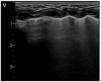

Lung ultrasound allows early detection of consolidations indicative of endotracheal tube (ETT) malposition (Fig. 5 A–B) or due to the decubitus position in patients with bronchopulmonary dysplasia (BPD). The combination of LUS findings and clinical manifestations increases the PPV of diagnosis of ventilator-associated pneumonia (VAP). A semiquantitative multiparameter score has been proposed for diagnosis of VAP that takes into account the most frequent sonographic findings of the disease: consolidations greater than 0.5 cm, bilateral consolidation, posterior consolidation, non-translobar consolidation and bronchogram (static, present in 100%, and dynamic, present in 70% of cases of VAP), highlighting the inability to completely reopen the consolidated area with the customary ventilation as a specific sign of VAP29 (Fig. 5C–F).

Detection of complications, forms of consolidation. A and B: Lung collapse/atelectasis due to endotracheal tube malposition. (A) Left anterior field: disappearance of pleural line with lung tissue hepatization and air bronchogram (hyperechoic, solid white arrow) and fluid (anechoic, hollow arrow). (B) Lateral field: absence of pleural line and hepatization, shred sign (hyperechoic border, boundary of collapsed lung/aerated lung) (star). (C) Preterm neonate born at 25+3 wk. Bronchopulmonary dysplasia. Consolidation/atelectasis in posterior field, disorganized bronchogram. (D) Same patient, follow-up ultrasound 2 h after change to prone position: resolution of consolidation. (E) Preterm neonate born at 23+5 wk, 50 h post birth, consolidation in left posterior field in the context of derecruitment. (F) Same patient at 35 days post birth, consolidation of homogeneous appearance in the clinical context compatible with ventilator-associated pneumonia.